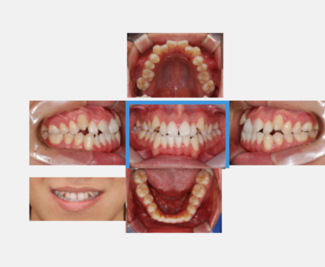

치과교정 분야에서 촬영 규격화된 임상사진 중 치과교정 및 보철분야 진단에 필요한 임상 정보 6종(구내사진 정면, 좌측면, 우측면, 상교합면, 하교합면 및 스마일 사진)에 대한 데이터셋

○ 환자별 이미지 종류

- 개구기 정면 이미지, 개구기 좌측 이미지, 개구가 우측 이미지, 교합면 상악 아미지, 교합면 하악 이미지, 스마일 이미지